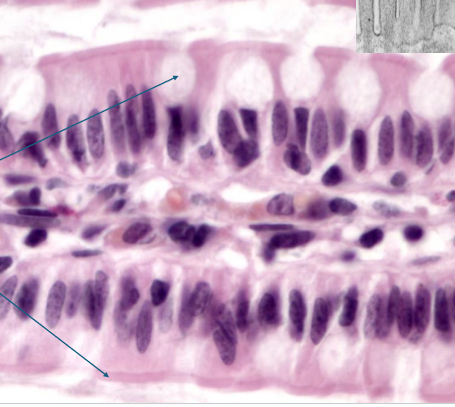

what is this?

PCCE

What is PCCE?

found in upper airway,s helps protect and move mucus

all cells attached to basement membrane, don’t all reach apical surface

lots of goblet cells

cilli on apical surface